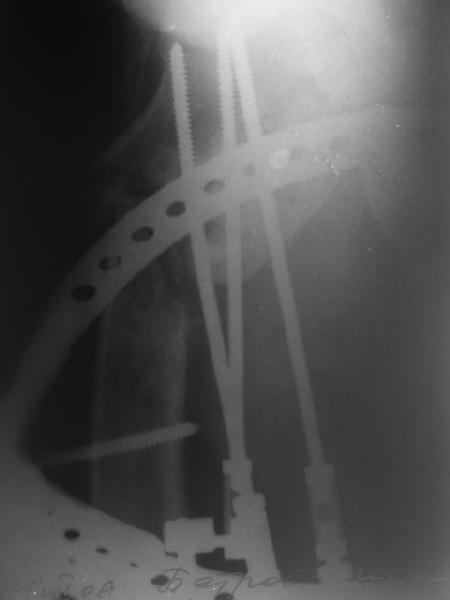

В приложении пример пациента, близкого по картине к тому, что представил Виктор (варус и смещение периферического отломка на поперечник кзади). Сделали как раз то, что Виктор исходно намеревался - аппаратная коррекция и затем гамма.